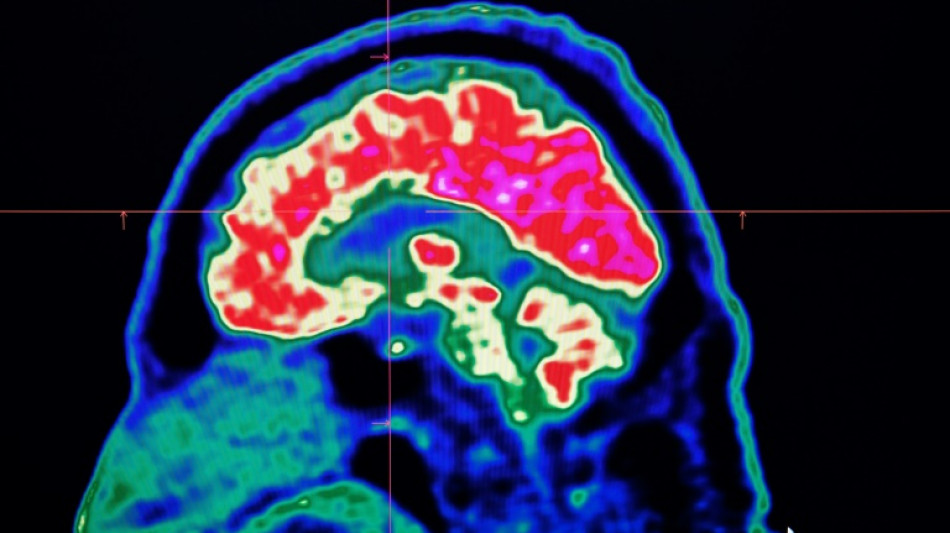

La inteligencia artificial reduce el riesgo de secuelas por un derrame cerebral / Foto: Fred Tanneau - AFP/Archivos

La inteligencia artificial ayuda en la toma de decisiones a la hora de interpretar los escáneres del cerebro y así permitir que los pacientes "reciban el tratamiento adecuado, en el buen lugar y en el buen momento", destaca el ministerio.